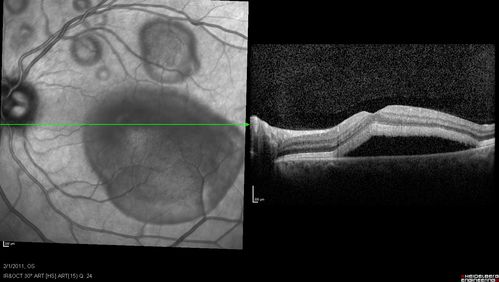

Acute Multifocal Vitelliform Exudative Maculopathy Left Eye At 1 Mo Follow Up

Acute Multifocal Vitelliform Exudative Maculopathy